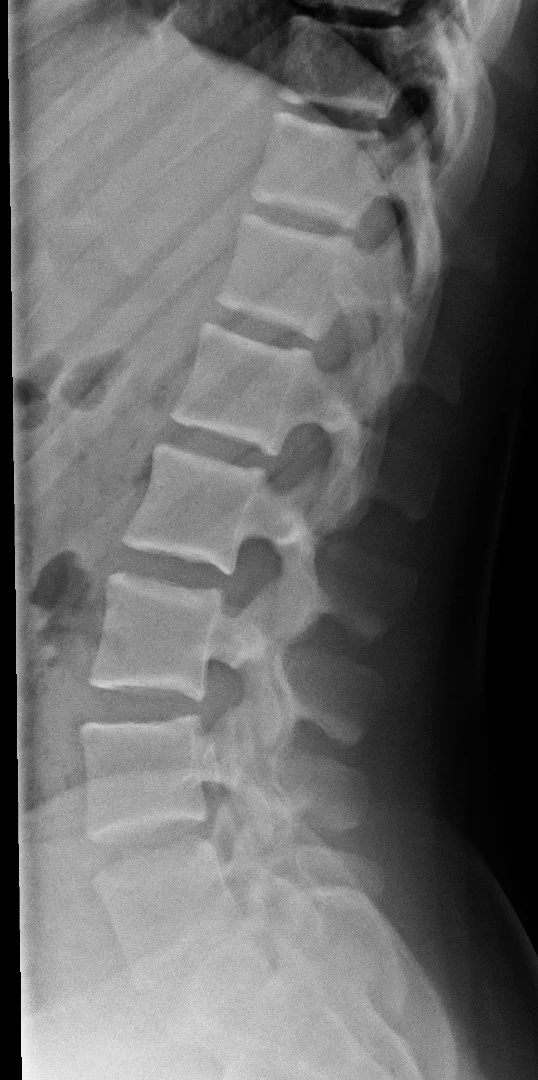

Extensive coverage of practically all possible radiograph presentations of both common and rare conditions in Chest, Abdominal and Musculoskeletal radiology have been included.

A similar depth of detail is given to MSK:

Master your FRCR 2B examination with authentic, expert-created content. Access 1,250+ short cases (2,000+ radiographs) across 50 packets, plus 600+ long cases (1,000+ cross-sectional images) in 100 packets. Every image is a full lossless DICOM at diagnostic workstation quality, following RCR display guidelines. No AI-generated content – all cases, questions, and answers are meticulously crafted by experienced radiologists.

2,000+ radiographs and 1,000+ cross-sectional images in full lossless DICOM format.

Zero AI content – all cases created by expert consultant radiologists.